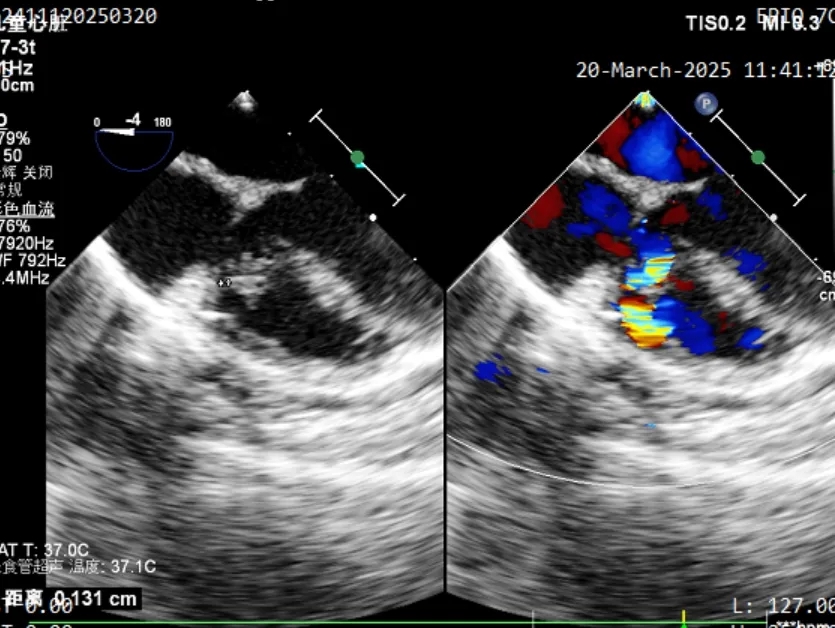

封堵器释放后评估

封堵器形态良好,无残余分流,封堵成功

术后1个月随访,二维超声心动图及心脏彩色多普勒所见:

5、室间隔见封堵器回声,位置固定,伞面光滑,塑性良好,室水平未见分流。

术中食道超声复测发现本例为膨出瘤型室缺并伴有多破口,瘤体基底宽约7.6mm, 两处破口分别宽约1.3mm和2.3mm。由于金属封堵器盘面展开易受膨出瘤限制,可能无法完全覆盖所有破口,存在残余分流风险。而全降解封堵器凭借其良好的柔韧性,植入后既能够自适应膨出瘤复杂的结构形态和组织运动,又可确保完全封堵。术者经综合考虑后,最终选择使用ABFDQ-I 5规格的全降解封堵器进行封堵。术后超声显示,封堵器形态良好,封堵完全,无残余分流。术后1个月随访,封堵器位置形态良好,患者恢复情况良好。